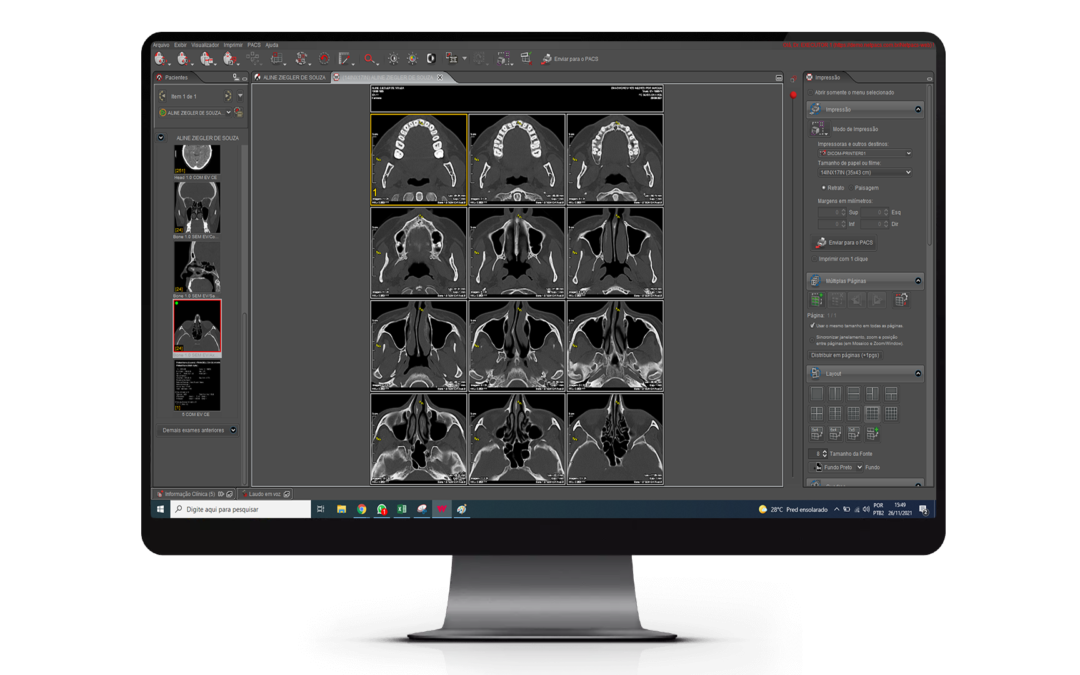

A impressão sob demanda com OCR A Impressão sob demanda é um recurso que permite a entrega ágil dos exames quando os pacientes já estão no centro de radiologia para retirar os resultados. Os nossos sistemas permitem a realização de impressão sob demanda de duas...

Impressão sob demanda na Animati Workstation A entrega dos exames aos pacientes e médicos solicitantes pode ser realizada de forma impressa ou digital. Em muitos casos, o acesso online e o envio do exame para o médico solicitante por e-mail, dispensa a necessidade de...

A impressão sob demanda A impressão sob demanda é um recurso que permite a realização da impressão de exames somente se houver a necessidade. Com o acesso a resultados online para o médico e paciente, a impressão de exames não é necessária sempre. Imprimir exames...